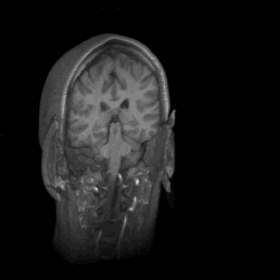

Wanna really see what's inside my head? Well, try not to get too grossed out! I created the movies below from anatomical data collected from a magnetic resonance image (MRI) scan. Special thanks goes to Sarah Creem for letting me participate in her psychology study, and for letting me get my hands on some of the resulting data.

A couple notes about this and the other pictures: First, my ears aren't really that big -- what you see is the foam from the ear protection I wore. (The MRI machine is loud!) You can faintly see the LCD goggles I was looking at during the experiment. The "wood grain" look of my head is a result of combining the multiple layers of data that the MRI machine takes. Also, I haven't shaved my head -- hair doesn't show up on the MRI. :)

The brief darkening half way through is the corpus collosum, the area between the hemispheres of the brain that doesn't have any tissue.